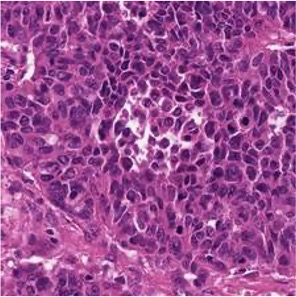

Multiple instance learning (MIL) is a powerful approach to classify whole slide images (WSIs) for diagnostic pathology. A fundamental challenge of MIL on WSI classification is to discover the \textit{critical instances} that trigger the bag label. However, previous methods are primarily designed under the independent and identical distribution hypothesis (\textit{i.i.d}), ignoring either the correlations between instances or heterogeneity of tumours. In this paper, we propose a novel multiplex-detection-based multiple instance learning (MDMIL) to tackle the issues above. Specifically, MDMIL is constructed by the internal query generation module (IQGM) and the multiplex detection module (MDM) and assisted by the memory-based contrastive loss during training. Firstly, IQGM gives the probability of instances and generates the internal query (IQ) for the subsequent MDM by aggregating highly reliable features after the distribution analysis. Secondly, the multiplex-detection cross-attention (MDCA) and multi-head self-attention (MHSA) in MDM cooperate to generate the final representations for the WSI. In this process, the IQ and trainable variational query (VQ) successfully build up the connections between instances and significantly improve the model's robustness toward heterogeneous tumours. At last, to further enforce constraints in the feature space and stabilize the training process, we adopt a memory-based contrastive loss, which is practicable for WSI classification even with a single sample as input in each iteration. We conduct experiments on three computational pathology datasets, e.g., CAMELYON16, TCGA-NSCLC, and TCGA-RCC datasets. The superior accuracy and AUC demonstrate the superiority of our proposed MDMIL over other state-of-the-art methods.